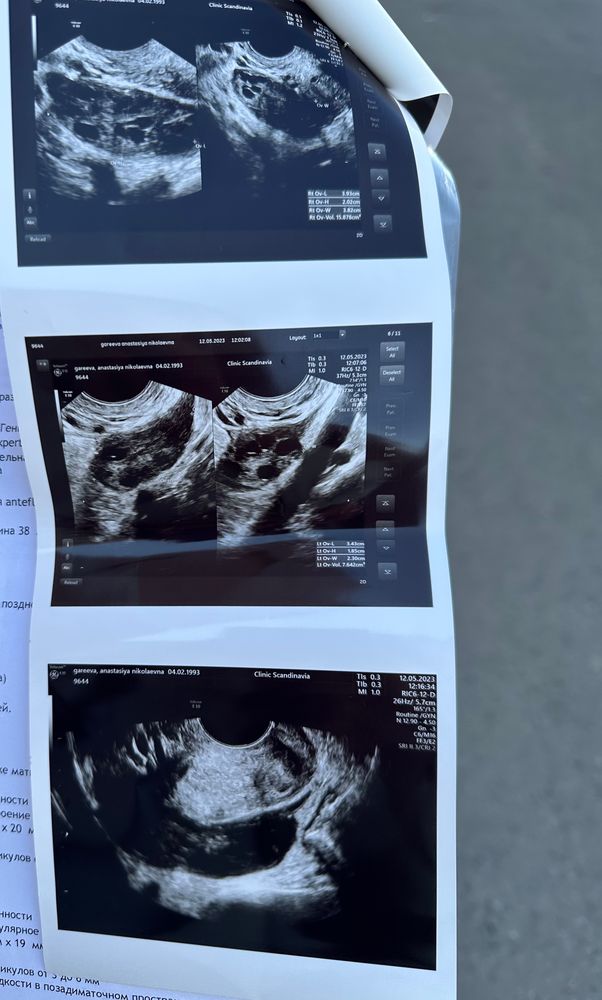

Образование рядом с яичником,за маткой

Анализы и процедуры. Помощь в расшифровке результатовКак думаете,что это может быть?Врач узи сначала не поняла,позвала вторую,решили,что киста..(при этом ошиблись с толщиной эндометрия).Правый яичник за маткой у меня.

.Моя РЕ(которой полностью доверяю)посмотрела снимки и сказала приехать,сделала узи и сказала,что в яичнике нет кист,это что-то рядом и отправила на МРТ

пс. У меня поликистоз